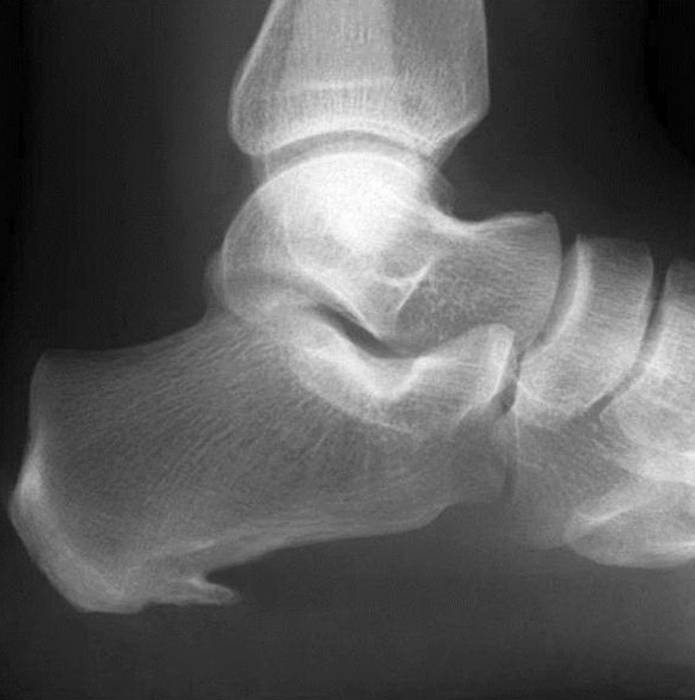

Eine Entzündung an der Fußsohle, genauer, am Ansatzpunkt der Plantarsehne zum Fersenbein. Als Folge einer längerfristigen Entzündung kann sich ein knöchernes Überbein (Sporn) bilden, dann reden wir vom Fersensporn.

Haglund-Exostose

Eine verstärkte Verknöcherung des hinteren oberen Sehnenansatzes der Ferse mit Beschwerden durch Druck des Schuhrandes.